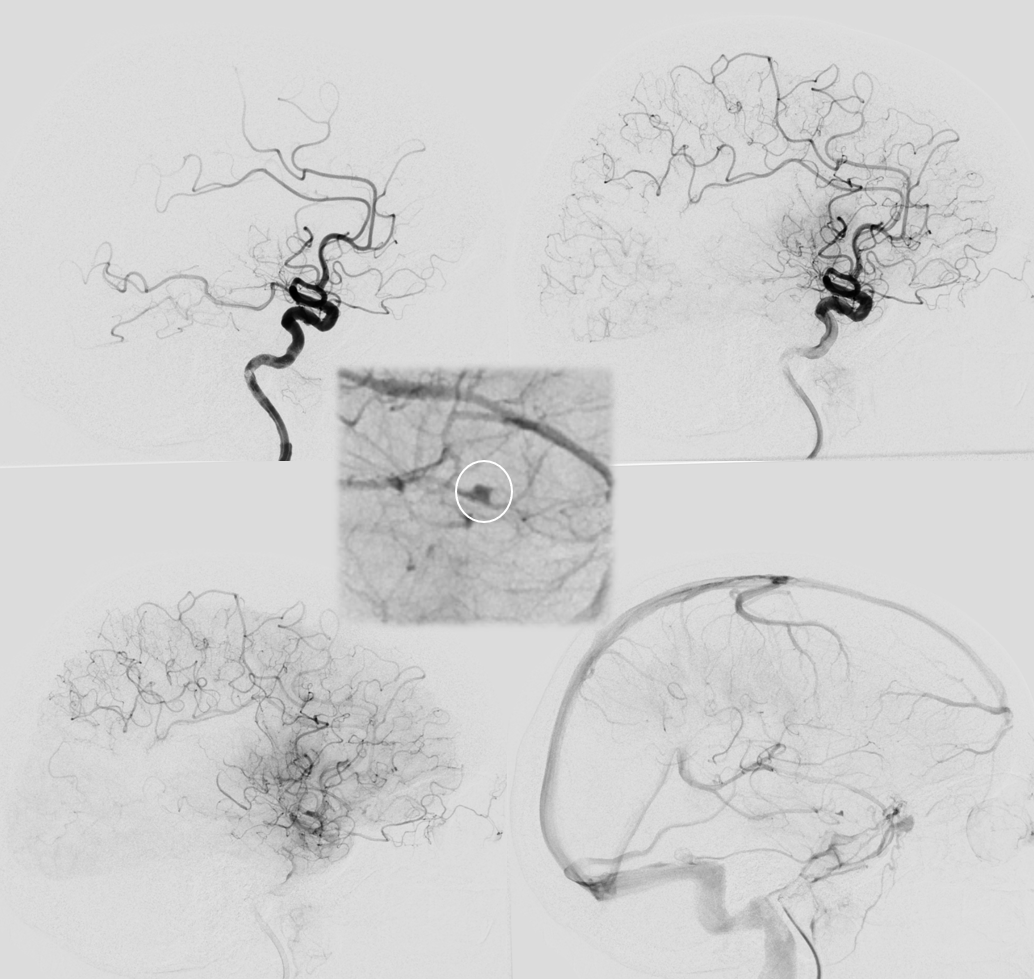

Now lets make a 3-5 mm thick MIP to see it better. We are looking at two occlusions. Each occlusion is at the distal end of the associated hyperdensity — where the contrast column stops (arrow – M2, dashed arrow — distal M2). Retrospectively one can see the distal occlusion on CTA, but not on catheter angio. Here we can definitively say that this is a tandem lesion, not a distal embolus after the upcoming proximal M2 aspiration.

As predicted there is a second occlusion. See correlation between angios and DYNA

Distal (MEVO) thrombectomy

Post. There is still one branch from this area (dashed arrow) missing plus another one in the inferior division